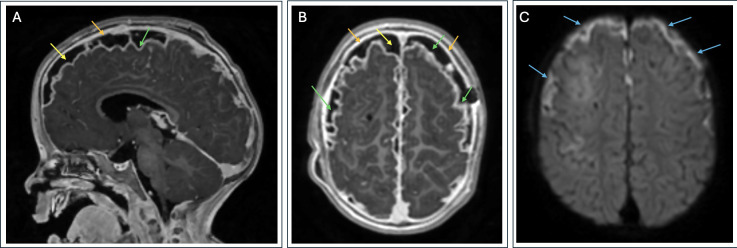

The Brief Case: How antibiotic pretreatment complicated the diagnosis of Haemophilus influenzae type a meningitis.

简短案例:抗生素预处理如何使a型流感嗜血杆菌脑膜炎的诊断复杂化。